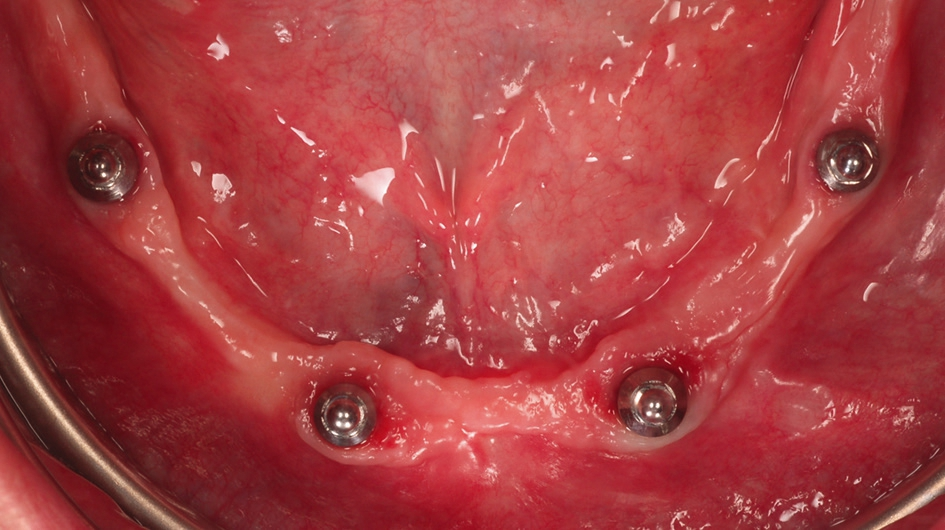

Nach einer weiteren siebenwöchigen Einheilungszeit wurden die Implantate freigelegt und mit Gingivaformern mit Platform Switch Ausführung (PS HP, BEGO Implant Systems) versorgt (Abb. 7).

Zur Befestigung herausnehmbarer, totalprothetischer Rekonstruktionen wurden in unserem Fallbericht Kugelkopfanker (PS BA, BEGO Implant Systems) und Locator®- ähnliche Easy-Con Aufbauten (PS Easy-Con, BEGO Implant Systems) verwendet. Kugelkopf-Attachments bestehen aus einer kugelförmigen metallischen Patrize (Abb. 8). Die Matrize wird in die Prothese eingearbeitet und kann aus Metall oder aus Kunststoff bestehen (Abb. 9). Die Vorteile des Kugelkopf-Attachments bestehen in der guten Hygienefähigkeit, den geringen Kosten und einer reduzierten Behandlungsdauer [7].

In unserem Patientenfall waren die Implantate annähernd parallel positioniert worden, so dass keine großen Abweichungen der Implantatachsen bestanden (Abb. 10). Es war ausreichend intermaxillärer Raum vorhanden und wir konnten den Patienten mit einer auf Kugelkopf-Attachments fixierten Unterkiefer-Cover denture Prothese versorgen. Das klinische Ergebnis war für Behandler und Patient gleichermaßen in optischer und funktioneller Hinsicht sehr zufriedenstellend (Abb. 11 und 12).

Auch das Easy-Con-System (PS Easy-Con) ist reparaturanfällig, da aufgrund von Retentionsverlusten der Austausch der Polyamid-Inserts erfolgen muss [26]. Da die Restaurationshöhe deutlich geringer ausfällt als bei den Kugelkopfankern, können die Easy-Con Aufbauten sehr gut bei einem geringen intermaxillären Abstand als Attachments verwendet werden. Easy-Con Aufbauten bestehen aus einer im Abutment integrierten Matrize aus Metall. Diese besteht aus einem erhöhten, ringförmigen Rand. Die aus Polyamid (Nylon) bestehende Patrize wird auf das ringförmige Abutment aufgesteckt und erhält ihre Retention sowohl über die Außenflächen als auch über die Innenflächen des Metallrings (Abb. 13). In die Prothesenbasis sind ebenfalls aus Polyamid gefertigte Einsätze eingearbeitet (Abb. 14). Durch die materialbedingte Elastizität der Easy-Con-Bestandteile verfügt das System über eine gute Elastizität/Resilienz (self-aligning) und ist in der Lage, sich den Bewegungen der Suprakonstruktion bei funktioneller Belastung gut anzugleichen [7]. Im Vergleich zum Kugelkopf-System können durch unterschiedlich konstruierte Patrizen axiale Disparallelitäten zwischen Implantaten bis zu einem Abweichungswinkel von 40 Grad ausgeglichen werden, ohne dass Retentionsverluste auftreten [37]. Auch mittels des Easy-Con-Systems konnte der Patient mit einer funktionell und optisch ansprechenden Cover denture- Prothese versorgt werden (Abb. 15).